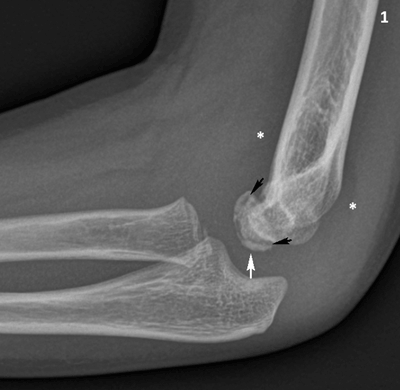

A seven-year-old boy presented with pain in his left elbow with a subtle swelling following a fall. There was a limited range of motion, mostly an extension deficit of the elbow. Conventional radiography (CR) of the left elbow (Figure 1) revealed joint effusion (asterisk) and irregular delineation of the articular contour of the capitellum with a radiolucent line in the subchondral bone (black arrows). There was also faint sclerosis of the capitellum (white arrows). Subsequent cone beam computed tomography (CT) (Figure 2) depicted a crescent-shaped subchondral vacuum phenomenon in the capitellum (black arrows). The diagnosis of Panner’s disease was made and the patient was treated conservatively, with rest, temporary immobilization and subsequent remobilization. The clinical follow-up was uneventful.

Conventional radiography of the right elbow, lateral view. The capitellum has a slightly irregular articular contour (white arrow) and there is a radiolucent line in the subchondral bone (black arrows). Note slight joint effusion with displacement of the elbow fad pads (asterisks).